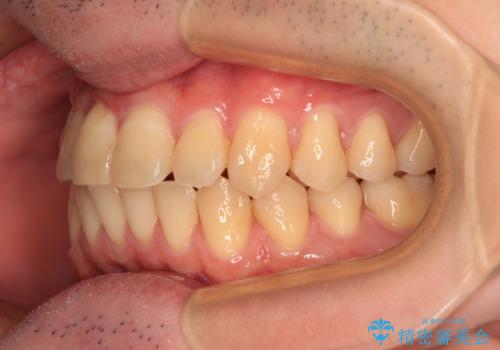

【モニター】前歯のデコボコとクロスバイト ワイヤー矯正で短期間に仕上げる

- 前歯のデコボコとクロスバイトを気にして来院された患者様です。

インビザラインでもワイヤー装置でも矯正治療は可能でしたが、煩わしい自己管理なしに短期間で治療を行いたいとのことで、目立たないワイヤー装置にて治療を行うこととしました。